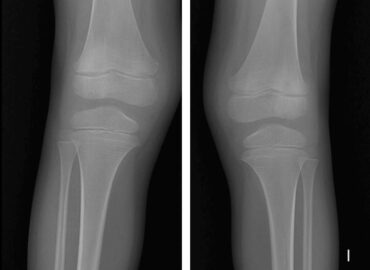

Caso 2 | Abril 2026 | Hospital Italiano

Masculino. 73 años. MC: Dolor unilateral en miembro inferior izquierdo de larga evolución (2 meses) que empeora los últimos días. […]